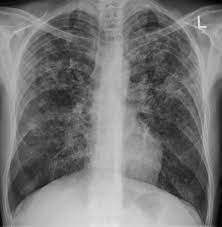

A general discussion of tuberculosis is found in the parent article: An exudative lesion, a proliferative lesion, and a fibrotic lesion, and because it may invade all the structure. Less than 50% of adults with primary tuberculosis. It may be a primary tuberculous infection, secondary infection or appear as chronic scarring. Pleural effusion on the same side is a common finding. The main tb bacterium is mycobacterium tuberculosis (m. Diagram of a treatment algorithm for active tuberculosis. The cdc states that a positive test for tb infection only tells that a person has been infected with tb germs. Primary tuberculosis may affect any part in the lung. This procedure is used as a secondary screening method in patients who have had a positive skin test and in patients who are at high risk for tuberculosis infection but have not had a positive skin test. Abnormalities on chest radiographs may be suggestive of, but are never diagnostic of tb, but can be used to rule out pulmonary tb. And some patients may show symptoms of cervical lymphadenectasis. Calcification is common but cavitation is unusual.

There is also suspicion of extrapulmonary tuberculosis, such as gastrointestinal or urogenital tuberculosis. It does not tell whether the person has latent tb infection (ltbi) or has progressed to tb disease. In postprimary tuberculosis, the most common imaging findings include cavitary lesions in which patients present with fever, night sweats, weight loss, and cough. Ltbi treatment must be delayed until active tb is ruled out. Thus, the differential diagnosis of pulmonary tuberculosis includes very many diseases.

Thus, the differential diagnosis of pulmonary tuberculosis includes very many diseases. Ltbi treatment must be delayed until active tb is ruled out. For decades, tuberculosis (tb), a potentially serious infectious lung disease, continues to be a leading cause of worldwide death. The appearance is typical for chronic pulmonary tuberculosis but may also occur with chronic pulmonary histiocytosis and chronic pulmonary coccidioidomycosis. An exudative lesion, a proliferative lesion, and a fibrotic lesion, and because it may invade all the structure. The samples are tested for tb bacteria. The cdc states that a positive test for tb infection only tells that a person has been infected with tb germs. This procedure is used as a secondary screening method in patients who have had a positive skin test and in patients who are at high risk for tuberculosis infection but have not had a positive skin test. Imaging findings for primary tuberculosis include pulmonary consolidation, effusion, and lymphadenopathy. A positive tb skin test or tb blood test only tells that a person has been infected with tb bacteria. This describes the person who has signs and symptoms of an active infection. Mri is the neuroimaging of choice for spinal tuberculosis. The main tb bacterium is mycobacterium tuberculosis (m.